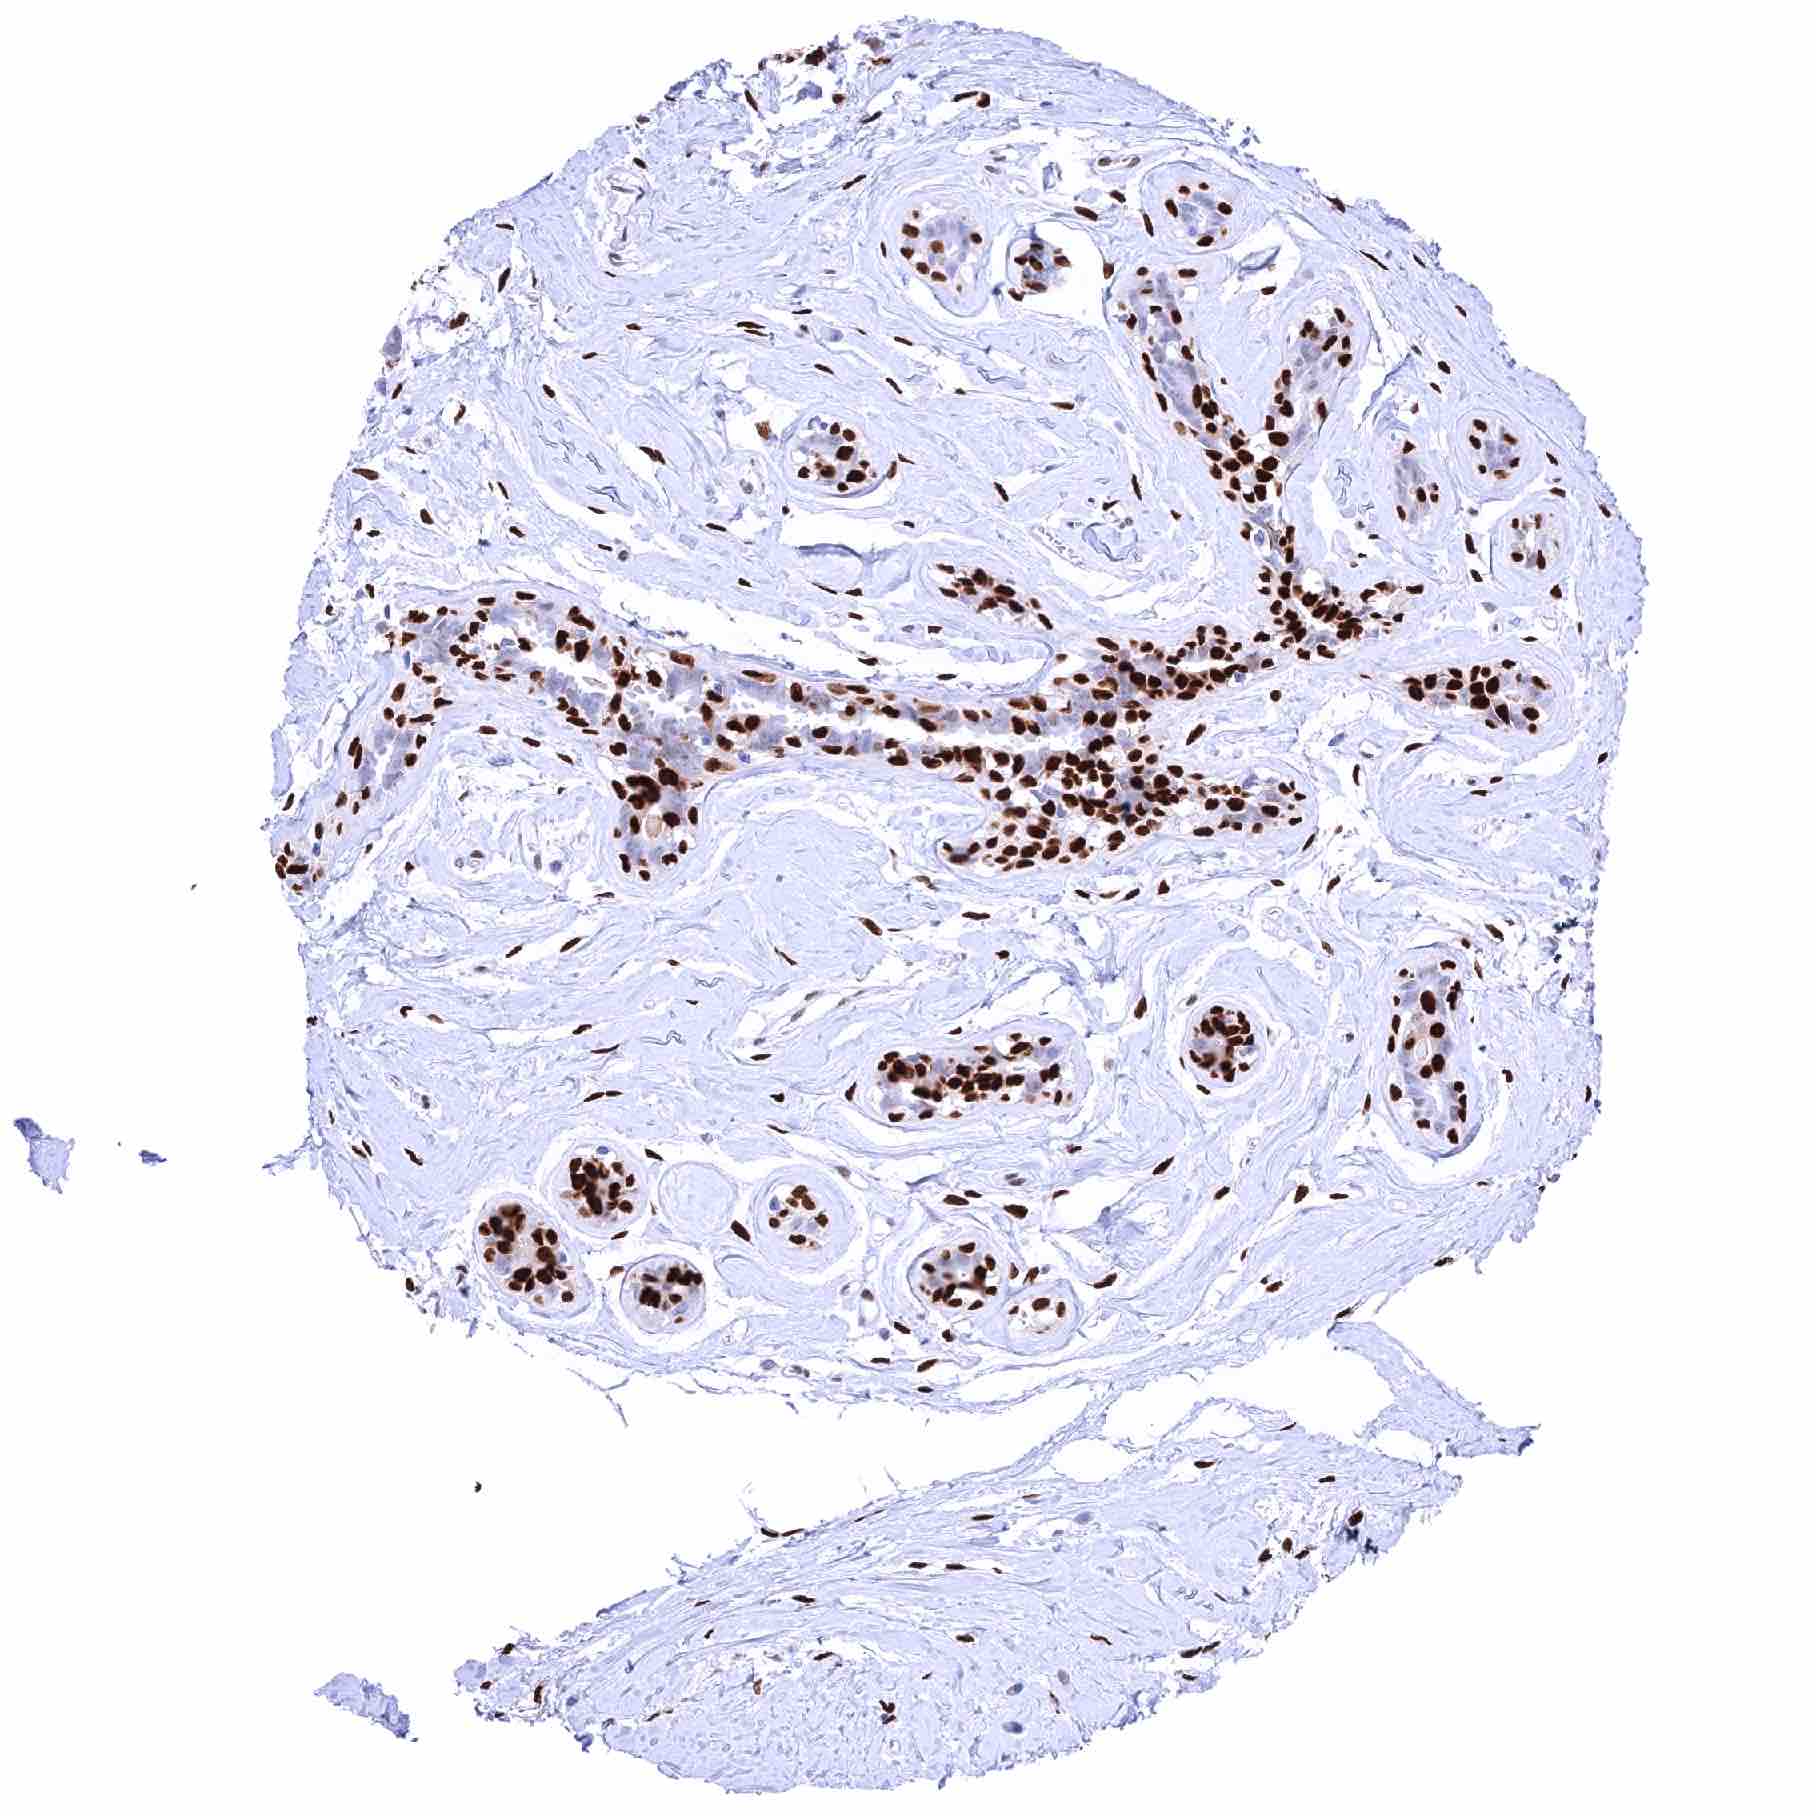

| Tonsil, surface epithelium – Significant decrease of nuclear NFIX staining of squamous epithelium from the basal-suprabasal to the superficial cell layers |